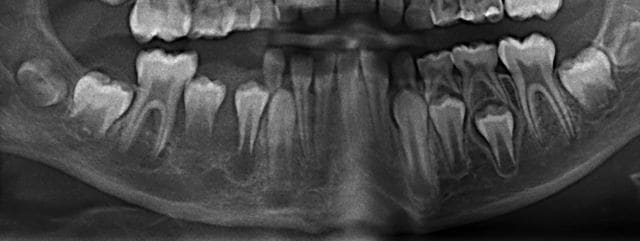

La 45 est bizarre, on dirait que la racine n'a quasiment pas été formée alors qu'elle n'est pas si profonde.

La radioclarté autour de 45 est douteuse.

Franchement, je ne vois pas en quoi 44 45 46 pourraient être mises en causes et l'apparence de radioclarté me semble plus liée à une ligne dense continue qui se prolonge en région symphysaire et qui s'apparente à un artéfact cinétique de la pano.

Ce serait quand même surprenant que sur les 2 panos il y ait eu un artéfact exactement au même endroit, et à l'endroit où on suspecte quelque chose.

il semble que l'absence de formation radiculaire de la 45 peut être due à la perte précoce de la 85

La 85 était très moche, c'est la porte d'entrée la plus évidente, qui a dû perturber l'évolution de 45.